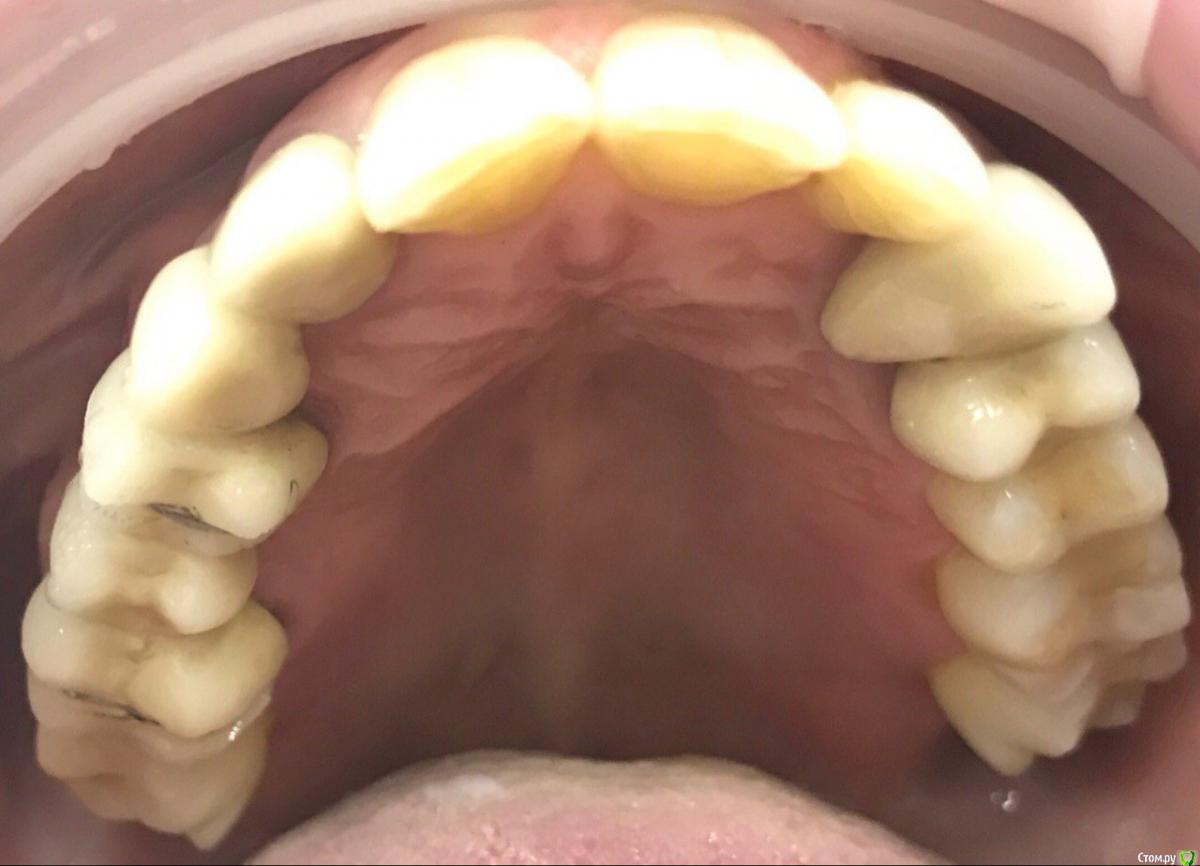

ksenistom Опубликовано 13 декабря, 2016 Поделиться Опубликовано 13 декабря, 2016 Пациентка И.,55 лет,хочет голливуд на обеих челюстях,в виде циркониевых коронок,справа сверху снят мостовидный протез,где установлены 2импл. неделю назад и удалён ретинированный клык в обл 13зуба(фото панорамы нет),поэтому эту сторону пока не трогаем,в области 46 планируется имплантация, 36зуб-вкладка+коронка,в области скученных нижних зубов сделан воксап.Вопрос в том,с чего начать?! Ссылка на комментарий